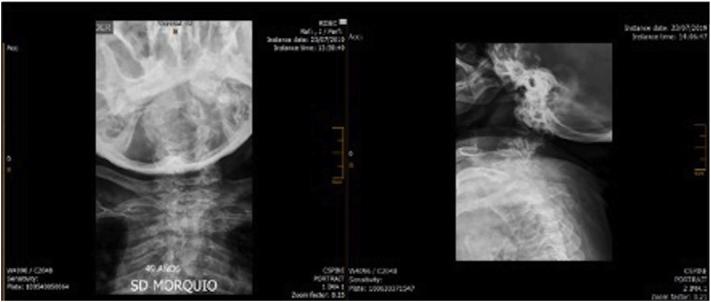

To present two female patients with Morquio A syndrome in their late adult years (over 50 years of age) with a classical phenotype, treated with enzyme replacement therapy; and to present a summary of the natural history and the characteristics of the disease, and the benefit of comprehensive management.

Enzyme replacement therapy with elosulfase alfa was effective, with an adequate safety profile in these two patients, showing evidence of sustained improvement in terms of endurance and gait patterns.

We present two cases of MPS IVA, with longer survival than reported previously in classical phenotypes associated with this disease condition. There is a paucity of reports of similar cases in the literature. We believe that the clinical heterogeneity of the disease manifesting with the classical phenotype, together with comprehensive management, have played a role in the survival of these two patients. Therapy with elosulfase alfa as part of comprehensive management has been crucial; we suspect a clinical response and infer a better quality of life and reduced burden for the caregiver, supporting its use in older patients.